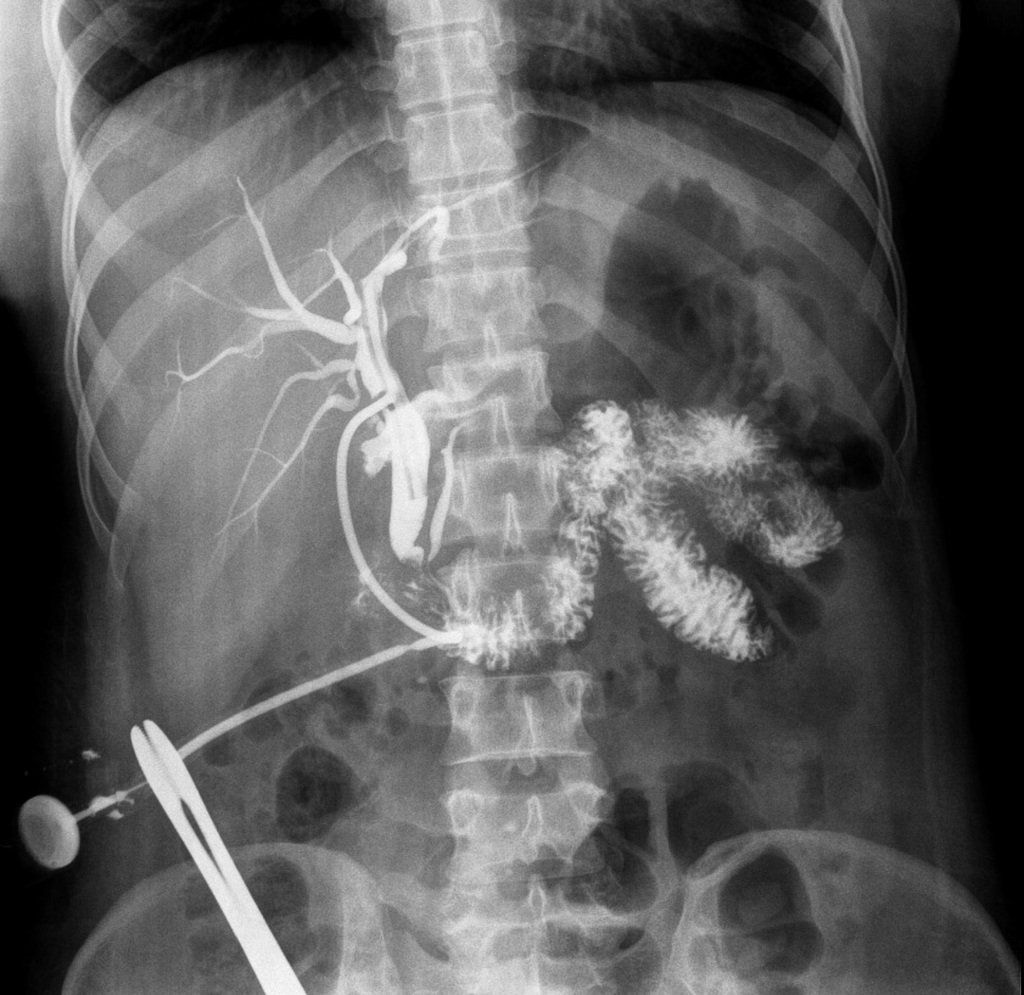

Chụp X-quang đường mật qua ống Kehr

Nguyên tắc của phương pháp chụp X-quang đường mật qua ống Kehr: Bơm thuốc đối quang có i-ốt tan trong nước vào đường mật, quá trình này sử dụng ống dẫn lưu Kehr (sau mổ) và thực hiện dưới màn tăng sáng hoặc không để khảo sát đường mật.

- Bác sĩ theo dõi trên màn tăng sáng khi mà thuốc lấp đầy toàn bộ đường mật thì yêu cầu người bệnh nín thở. Lúc này tiến hành chụp và chẩn đoán sơ bộ nhằm chọn các tư thế cần thiết để bộc lộ những tổn thương trong đường mật.

Yêu cầu về kết quả chụp phim

- Điều chỉnh độ đối quang phù hợp

- Bản phim phải bộc lộ được toàn bộ hình ảnh đường mật và phía ngoài gan.